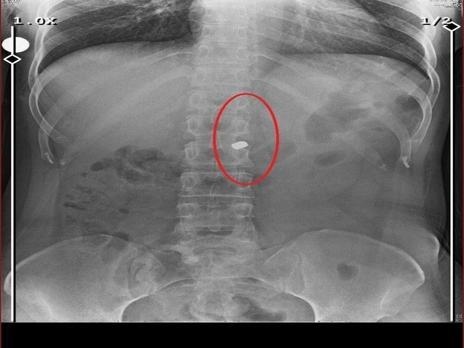

Cinayetin ardından aynı silahı sevgilisine çeviren Sarıkaya, Fatma O.'yu 8 kurşunla yaraladı. Olayın ardından arkadaşı Özaslan'ın cesedini önce çarşafa, ardından kokuyu engellemek amacıyla streç filme sarıp bantlayan zanlı, evde dehşet verici bir düzen kurdu. Yaralı haldeki sevgilisinin hastaneye gitmesine izin vermeyen Sarıkaya, eczaneden aldığı sargı bezi ve ilaçlarla kadına pansuman yaptı. İddianameye göre Sarıkaya, yaralı halde evde rehin tuttuğu Fatma O.'ya 21 gün boyunca cinsel saldırıda bulundu.